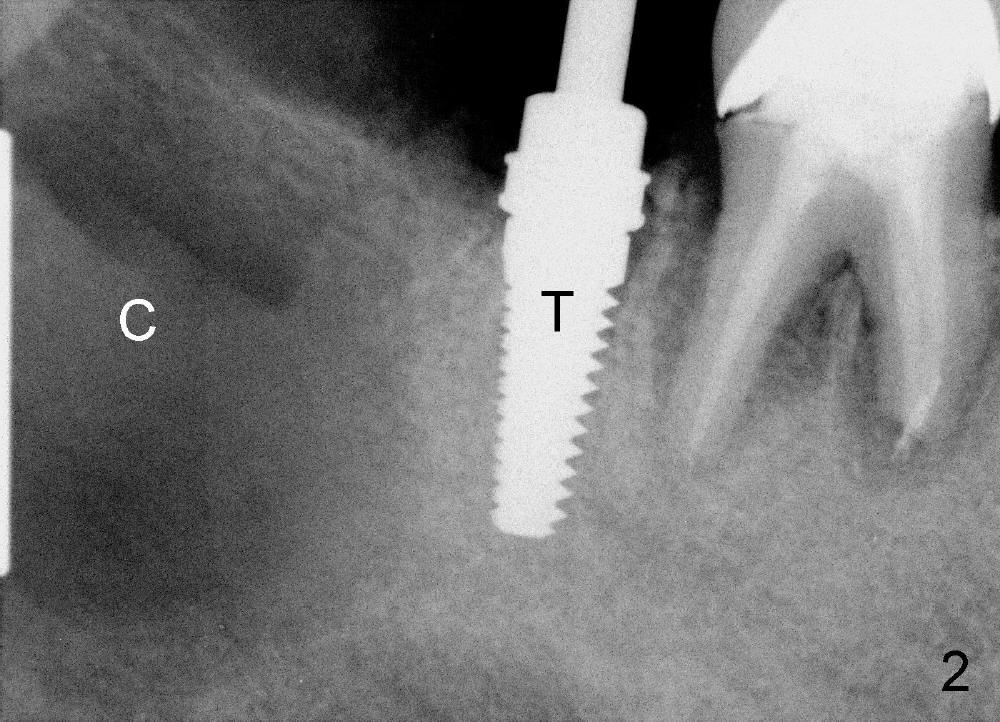

A 47-year-old man has poor dentition (Fig.1).  The tooth #31 is non salvageable.  It has two roots.  There is a dentigerous cyst (C) associated with #32.  There is no apparent bone distal to the distal root of the 2nd molar.